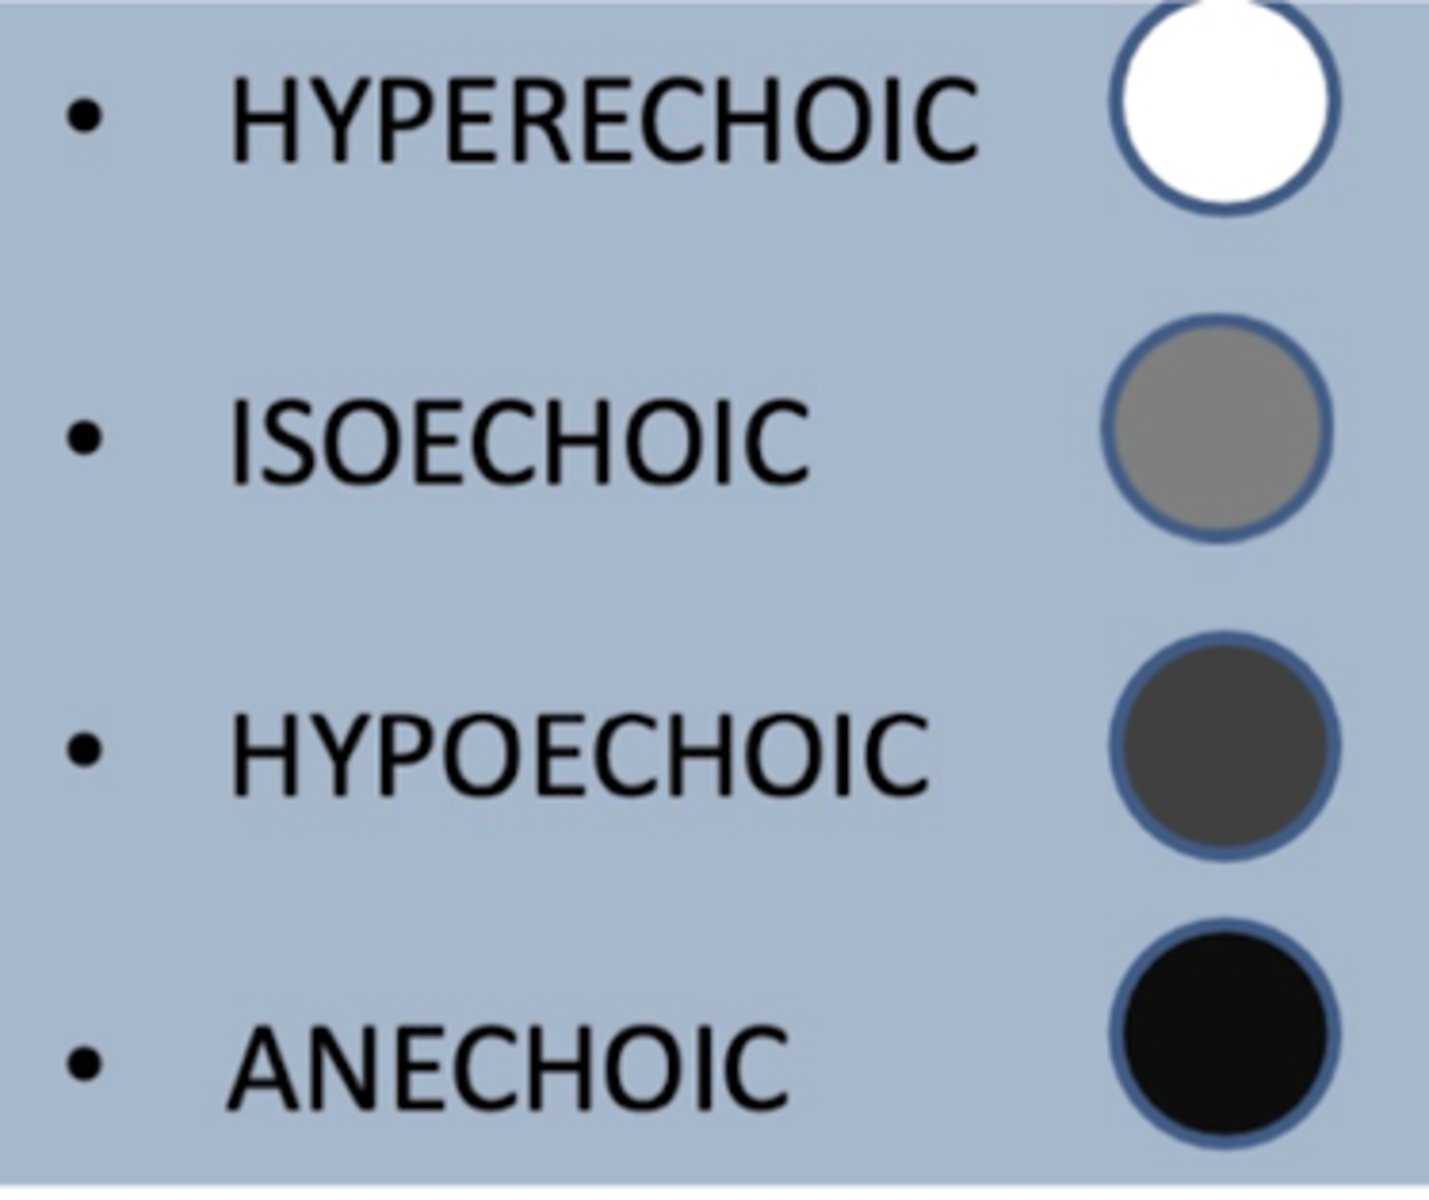

ultrasonography

this terminology is used for what type of imaging technique?

anechoic

in an ultrasound, a structure that appears black is called...

isoechoic

in an ultrasound, a structure that appears light grey is called...

dark grey

in an ultrasound, a structure that is hypoechoic appears in what color...

hyperechoic

in an ultrasound, a structure that appears white is called...